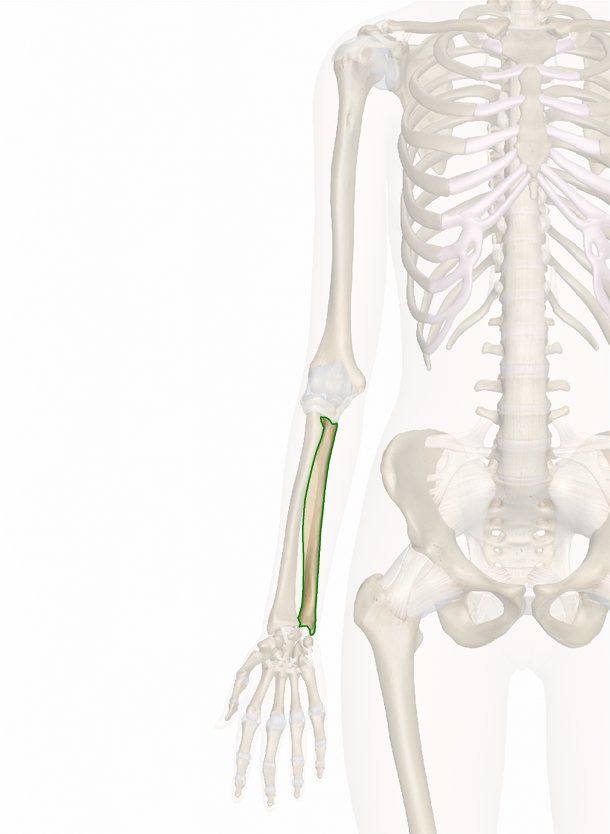

Локтевая кость также обладает трехгранной формой. Верхний проксимальный участок кости имеет характерное утолщение, на котором спереди расположена блоковидная вырезка, которая необходима для сочленения с плечевой костью, латеральный край имеет лучевую вырезку, которая в свою очередь служит для сочленения с головкой лучевой кости. Ниже переднего отростка расположена бугристость локтевой кости, именно к ней прикрепляется плечевая мышца. Дистальный конец локтевой кости образует утолщение, его название — головка локтевой кости. На лучевой стороне дистального конца находится суставная поверхность. Она необходима для сочленения с лучевой костью. Локтевая кость на всем своем протяжении (от локтевого отростка до шиловидного) также легко ощущается под кожей. На верхней передней части кости расположены мышцы, в нижней части — сухожилия.

Лучевая кость характеризуется тем, что утолщение находится не на верхнем, а на нижнем конце. У верхнего конца имеется головка лучевой кости, которая обращена в сторону плечевой кости. По краю головки кости расположена суставная окружность, она необходима для сочленения с локтевой костью. Немного ниже головки у лучевой кости находится наиболее суженное место, оно называется шейкой лучевой кости. Немного ниже шейки расположена довольно выраженная бугристость, она является местом прикрепления сухожилий двуглавой мышцы плеча. Эпифиз (нижний конец) лучевой кости имеет запястную суставную поверхность, она сочленяет его с костями запястья. Снаружи эпифиза имеется латеральный шиловидный отросток, хорошо прощупываемый под кожей, а изнутри — локтевая вырезка, сочленяющая конец с головкой локтевой кости. Края локтевой и лучевой кости острые и обращены друг к другу, благодаря этому обеспечивается ограничение межкостного пространства, именно поэтому они называются межкостные края.

Большая часть лучевой кости расположена среди мышц, под кожей хорошо прощупываются такие отделы:

- Сзади и ниже латерального края мыщелка плечевой кости — головка;

- Снизу — латеральный шиловидный отросток;

- Снаружи, сзади и частично спереди расположен нижний отдел.

Описание костей предплечья — локтевая кость

Локтевая кость длиннее, больше нижней кости руки — лучевой. Многие мышцы плеча и предплечья прикрепляются к этой кости для выполнения движений руки, кисти и запястья. Движение локтевой кости имеет важное значение для таких повседневных задач, как бросок мяча езда за рулем автомобиля.

Локтевая проходит через предплечье от локтя до запястья, значительно сужается в направлении дистального конца. На ее проксимальном конце образуется сустав с плечевой костью в плече и лучевой предплечья. Она проходит мимо плечевой кости в виде кончика локтя, известного как отросток … [Читайте ниже]

Направляясь дистально от локтевого сустава, кость начинает слегка сужаются в диаметре по всей длине, а также медиально изгибаться. На дистальном конце образуется небольшая часть запястья с лучевой и кистью руки. Закругленный отросток, известный как головка, образует дистальный лучелоктевой сустав с вогнутой локтевой вырезкой. Выравнивание этих совместных структур позволяет лучевой вращаться вокруг локтевой в запястье. Небольшое костное расширение, известное как шиловидный отросток выступает из заднего и медиального угла и обеспечивает точку крепления для локтевой коллатеральной связки запястья.

Локтевая кость — парная кость предплечья, которая формируется тремя краями: передним, задним и латеральным и двумя эпифизами. Шейка пролегает спереди между телом и верхним концом. Верхний край локтя продолжается локтевым отростком. Снизу находится головка с суставной поверхностью для соединения с запястьем. Головка суставной окружностью сочленяется снаружи лучевой кости. На внутренней стороне головки лежит шиловидный отросток.